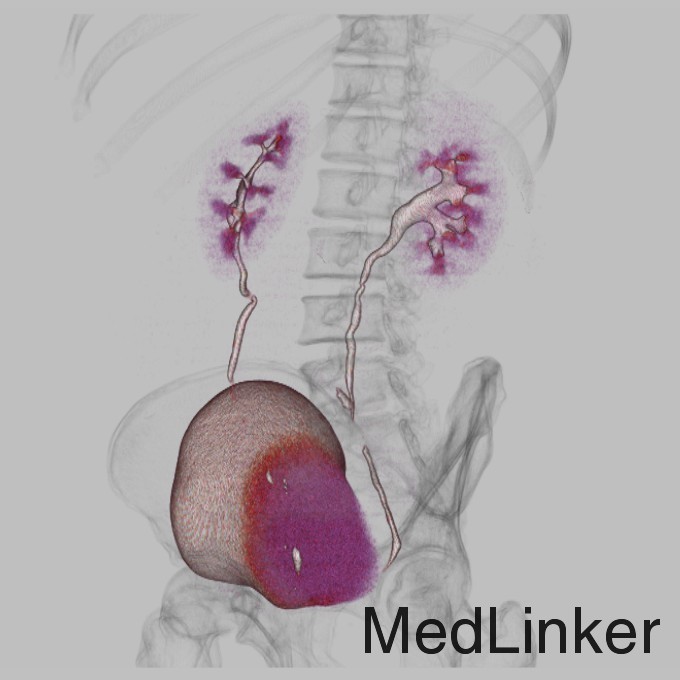

查体:肛门括约肌稍松弛,前列腺明显增大,大小约:4×3cm,表面光滑,质韧,边缘清楚,中央沟变浅,未触及明显结节,指套未见染血。 辅查:CT示:右侧输尿管下段软组织肿块影,考虑输尿管癌可能,相应输尿管中上段、右肾肾盂扩张积水

诊断:输尿管癌? 治疗:经术前准备,行右侧输尿管镜镜检+肿物活检术,手术顺利,术后病理示:高级别浸润性尿路上皮癌。与家属充分沟通及完善术前准备后,行腹腔镜下右肾、右输尿管癌根治性切除术,手术顺利,术后恢复较好,术后病理示:符合高级别浸润性尿路上皮癌。

讨论:输尿管恶性肿瘤多来源于输尿管上皮组织,以移行细胞癌最常见,移行细胞癌多呈乳头状生长,突入腔内,约1/3为多发性肿瘤。影像表现为输尿管、肾盂和肾盏不同程度扩张积水,并于输尿管梗阻端发现软组织肿块或腔内有充盈缺损,增强扫描轻中度强化,集合临床表现,多可作出诊断,不过应注意输尿管癌的多发性,勿漏诊!